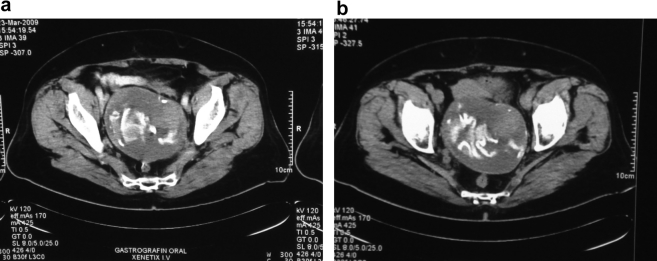

A 68 year old, Caucasian lady presented to urology department suffering from acute urinary retention. There were no LUTS (Low Urinary Track Symptoms) in her history and she did not mention recurrent Urinary Tract Infections (UTI's). The patient underwent intermittent catheterization and 530 mL of urine were evacuated. The drop strip test was negative for nitrates and leukocytes and all the other parameters were in the normal area. Patient got the recommendation to evaluate the urinary tract by U/S. Eight hours later she had a recurrent retention. The U/S revealed a medium degree of hydronephrosis in left kidney and a mass at the left side of the small pelvis which pushed forward the uterus and the bladder. An ovarian or intestinal tumor was suspected and patient evaluated further with CT scan, tumor markers measurement and colonoscopy. CT scan revealed a mixed (solid and cystic) mass (Fig. 1a and b), with diameter of 12 cm with interpretation of the left ovary. All tumor markers were negative. Colonoscopy was normal, as well. The patient underwent laparotomy and the mass was excised after a difficult dissection due to severe adhesion between the mass and the bowel. No enterectomy was required. The well-capsulated mass was a retained surgical sponge. The patient had undergone cesarean procedure 29 years ago.

Figure 1.

(a and b) CT scan revealed a mixed (solid and cystic) mass, with diameter of 12 cm.